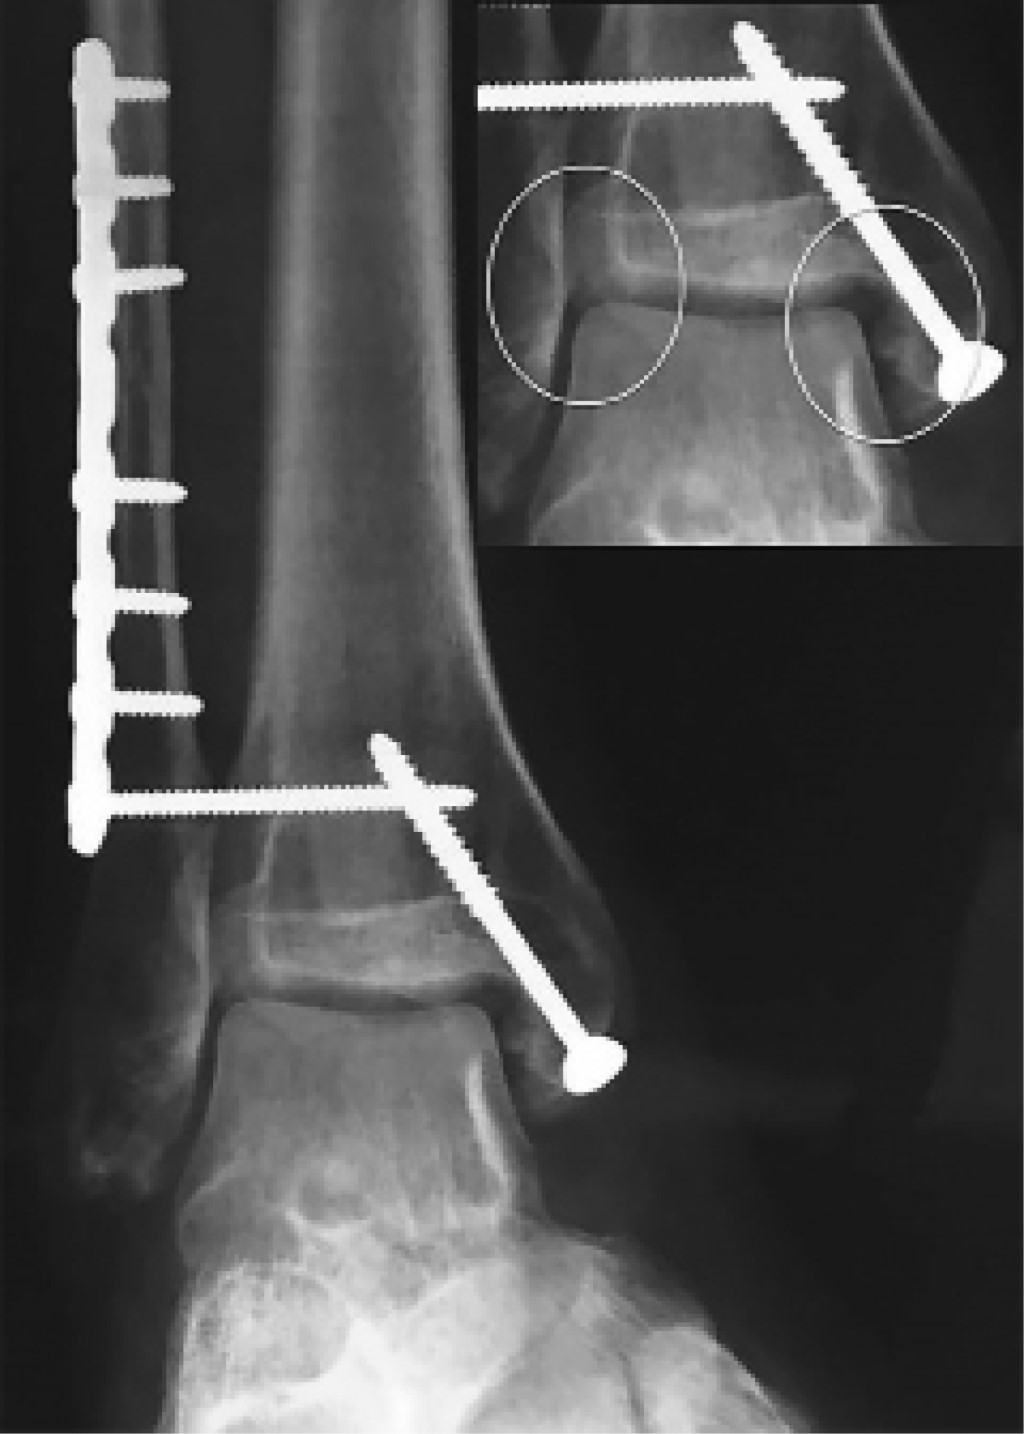

The AP ankle radiograph (Figure 2) showed an apparent congruent joint with a symmetrical clear space between the tibial articular surface and the talar dome, without internal augment. On a second look, an irregularity on the lateral facet of the medial malleolus could be noticed, as well as the incorrect vertical alignment between the tibia and the talus (Figure 2, zoom with circles).

The CT Scan confirmed a medial malleolus rotational malunion with a bone fragment that blocked the ankle dorsiflexion. There was also a talar lateral translation causing tibiotalar incongruency and syndesmosis malreduction, with diastasis (Figure 3).

The patient was submitted to hardware removal but the dorsiflexion block persisted. As our goal was to remove the dorsiflexion mechanic block and to restore tibiotalar congruency, we decided to perform the "box resection" (Figure 4 and 5). This allowed an immediate medial talus translation. A syndesmosis debridement and open reduction with a clamp was performed and stabilized with a flexible system (TightRope® Arthrex). We conducted a deltoid ligament re-insertion with anchors (Figure 6). At the end of the procedure, complete dorsiflexion was accomplished with a stable range of motion. Tibiotalar congruency was confirmed in the AP radiograph (Figure 7).